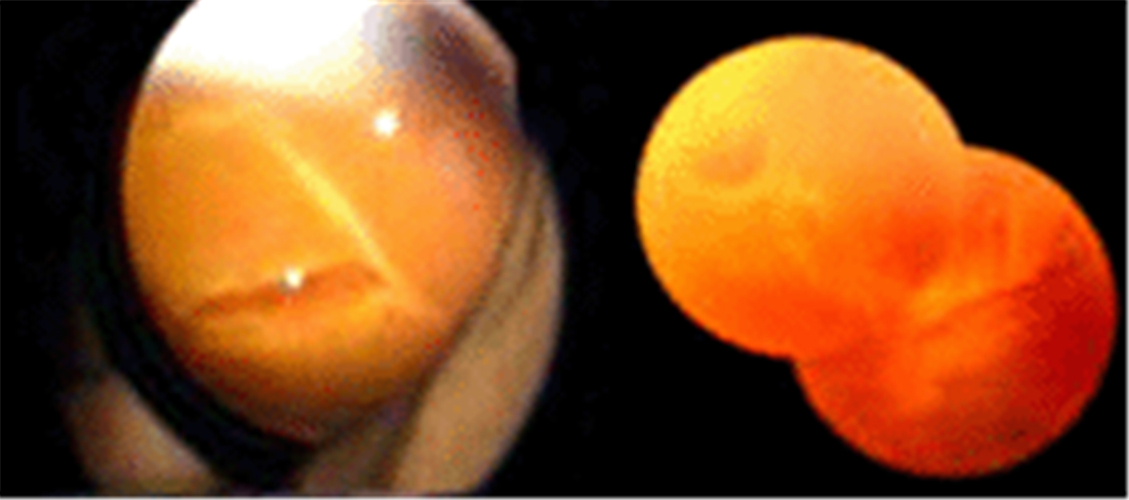

早產兒視網膜脫落

早產兒牽拉性視網膜脫落